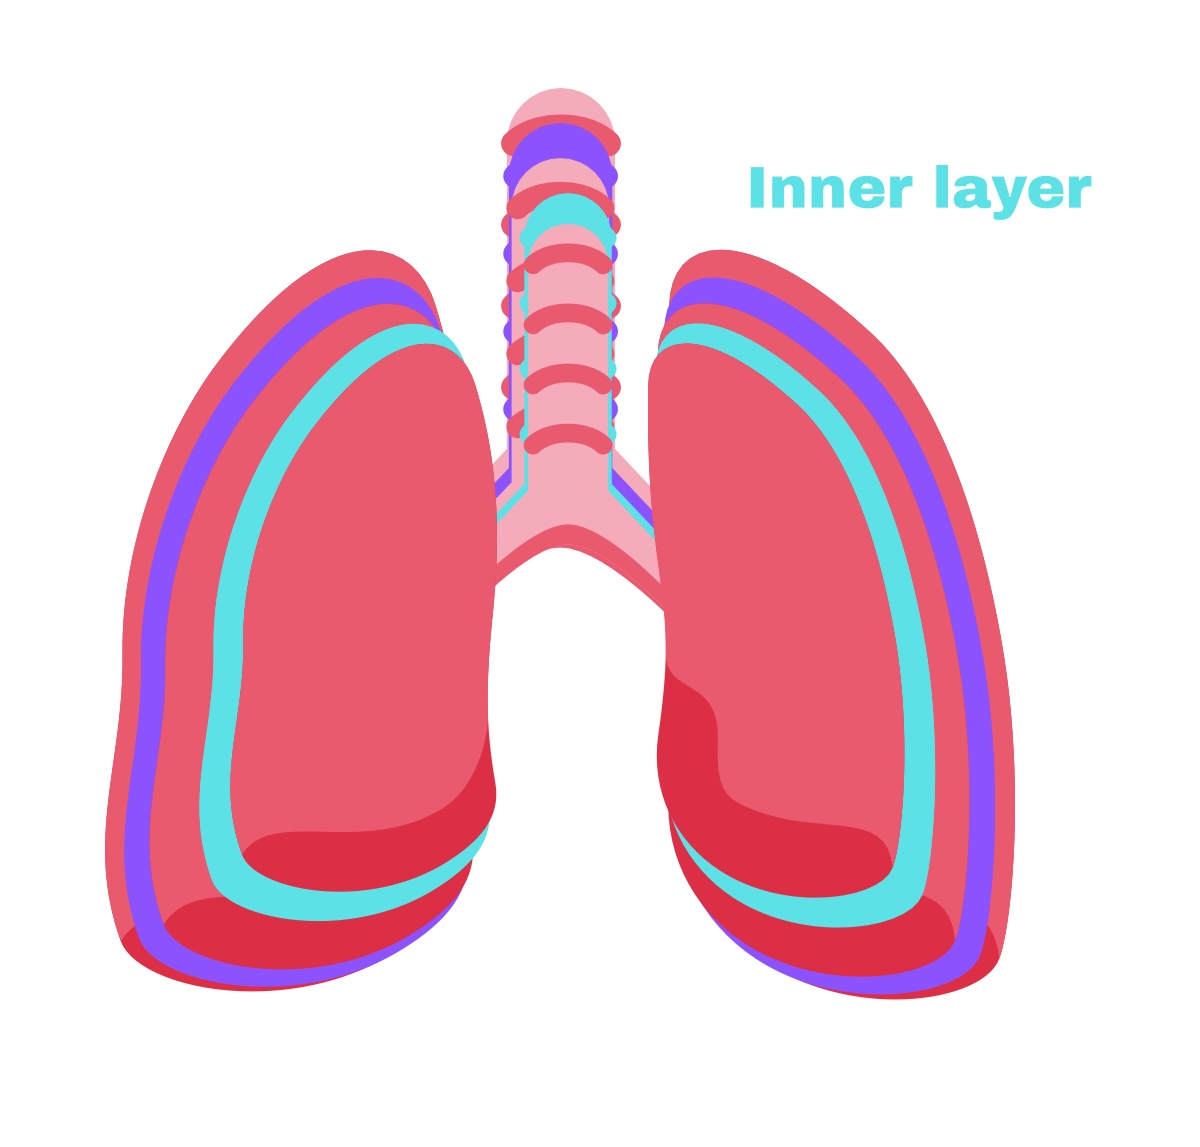

Visceral pleura

Deep layer (surface of organ)